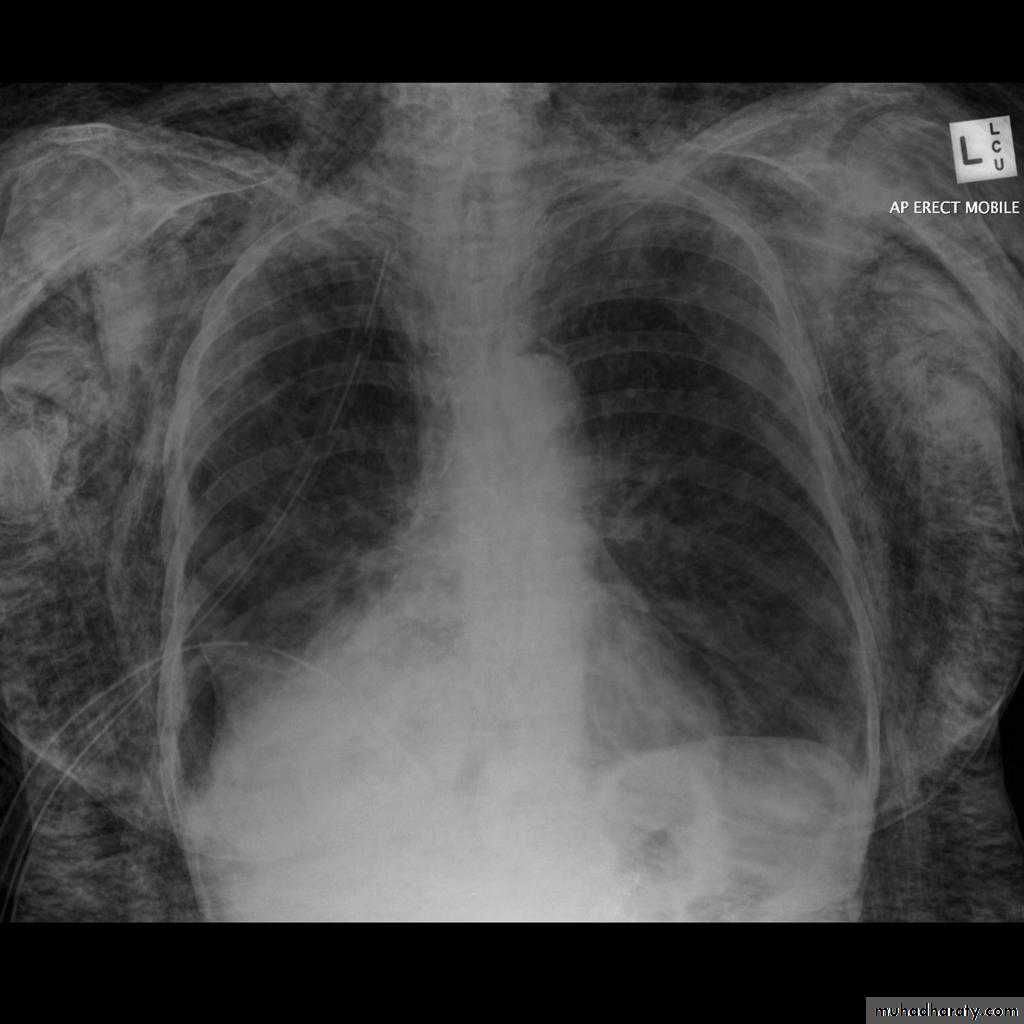

PneumothoraxPneumothorax refers to the presence of gas (air) in the pleural space. When this collection of gas is constantly enlarging with resulting compression of mediastinal structures it can be life-threatening and is known as a tension pneumothorax

A pneumothorax is, when looked for, usually relatively easily appreciated. Typically they demonstrate:

visible visceral pleural edge see as a very thin, sharp white line

no lung markings are seen peripheral to this line

the peripheral space is radiolucent compared to adjacent lung

the lung may completely collapse

the mediastinum should not shift away from the pneumothorax unless a tension pneumothorax is present

A tension pneumothorax

A tension pneumothorax occurs when intrapleural air accumulates progressively in such a way as to exert positive pressure on mediastinal and intrathoracic structures. It is a life threatening occurrence requiring rapid recognition and treatment is required if cardiorespiratory arrest is to be avoided.Radiographic features

A pneumothorax will have the same features as a run-of-the-mill pneumothorax with a number of additional features, helpful in identifying tension. These additional signs indicate over expansion of the hemithorax:

ipsilateral increased intercostal spaces

shift of the mediastinum to the contralateral side

depression of the HYPERLINK "http://radiopaedia.org/articles/diaphragm" hemidiaphragm